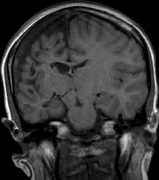

syndrome in 1926. The term von Hippel-Lindau syndrome (VHL) was

first used in 1936.166 The first major clinical criteria for the syndrome were proposed in 1964.167 The main manifestations of von Hippel-Linau syndrome are: histologically similar hemangiomas of the retina and CNS, renal cysts, renal cell carcinomas, pancreatic cysts, pheochromocytomas, and endolymphatic sac tumors.13 EPIDEMIOLOGY The prevalence of VHL syndrome is about 1 in 35,000 to 40,000.168 It is autosomal dominant with greater than 95% penetrance by age 60 years.169 Its expression, even within the same family, may be quite variable, especially for renal disease and pheochromocytoma.170,171 SYSTEMIC FEATURES Cutaneous Findings Cutaneous findings are not part of the diagnostic criteria for VHL syndrome. Neurologic Findings CNS hemangiomas are the most common tumor of VHL, affecting 60% to 80%, with a predilection for the cerebellum and spinal chord. An enlarging cystic component is a frequent finding in symptomatic tumors. Patients typically present in their early 30s; headaches or neck pain in affected individuals should not be ignored.172,173 On microscopy, CNS hemangiomas resemble retinal capillary hemangiomas. Their malignant potential is low.174 The treatment is surgical (Fig. 17, A and B).13 Endolymphatic sac cystadenomas are a sensitive marker of VHL. Patients may present with hearing loss, tinnitus, disequilibrium or facial nerve palsy.175,176 Visceral Findings KIDNEY. Renal cysts are often asymptomatic and do not require treatment. However, complex cysts may carry a risk for malignant transformation. Renal carcinoma affects about a third of patients. Patients typically present in their late 30s. These tumors may be completely asymptomatic, underscoring the necessity for ultrasound screening.13,177 ADRENALS. Pheochromocytomas are benign neural crest tumors of the adrenal medulla (chromaffin cell derived) and probably affect 10% to 20% of patients. Mean age at diagnosis is at about 30 years of age. Pheochromocytomas may be multiple and bilateral. They are catecholamine-secreting tumors that classically produce severe hypertension and anxiety attacks, but they may also be asymptomaic.178 The National Cancer Institute classification of VHL syndrome is in part based on the absence (type I) or presence (type II) of pheochromocytoma (Table 5).171